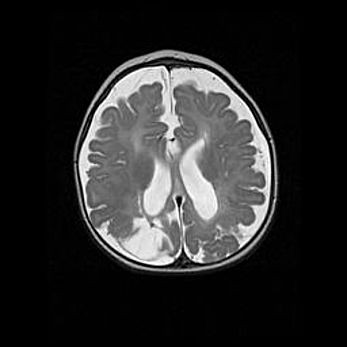

Неполная лизэнцефалия (пахигирия). Открытая гидроцефалия.

Возраст: 17 дней

Вес: 3110 г

Пол: мужской

Окружность головы: 33,5 см

Срок гестации: 35-36 недель

Лизэнцефалия—недоразвитие корковой пластинки и мозговых извилин в результате нарушения миграции нейронов коры. Поверхность мозговых полушарий гладкая. Микроскопически выявляется отсутствие нормальных слоев коры и скопление групп нейронов в подкорковом белом веществе.

Пахигирия—уменьшение числа вторичных извилин. В пораженном полушарии нервные клетки образуют толстый недифференцированный слой с неправильно расположенными нервными волокнами и группами гетеротопных клеток. Нервные клетки незрелые. Белое вещество истончено. При этом нередко аномально развит корково-спинномозговой путь.